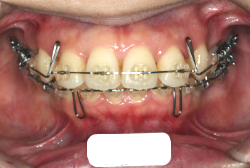

「乳歯が生え替わらない」という主訴で来院したケースです。 診断の結果、「左上永久犬歯が第一小臼歯後方上部に埋伏しているため、左上乳犬歯が晩期残存している症例」と判明しました。

このような症状の場合は、手術で埋伏している永久歯に金具を取り付け、矯正装置で牽引する必要があります。同時に凸凹の解消と前突した前歯を内側に入れるために上下左右の小臼歯を抜歯させて頂くことといたしました。

この方の場合は、マルチブラケット装置にて治療を開始し、治療期間2年3ヶ月で終了しました。犬歯の牽引距離が非常に大きかったため当院の平均治療期間よりも大幅に期間がかかりましたが、埋伏犬歯を完全に正しい位置まで誘導することができました。同時に 前歯の前突と配列の凸凹も解消しました。

マルチブラケット装置は、装置装着時より数日から2週間程度強い不快感疼痛が有りますが、本症例場合は埋伏歯を開窓手術し、遠く離れた位置に矯正器具が付いていますので強い違和感が生じ、歯ブラシも届きにくく口腔衛生状態を保つのにはかなりの努力が必要です。条件の悪い場所に接着されているため、装置が外れやすく日常生活上もかなり配慮が必要となります。

また、埋伏歯は移動距離が大きくなることが多く、歯根吸収のリスクが高まりますので、移動と休止にゆとりのある治療間隔が必要です。